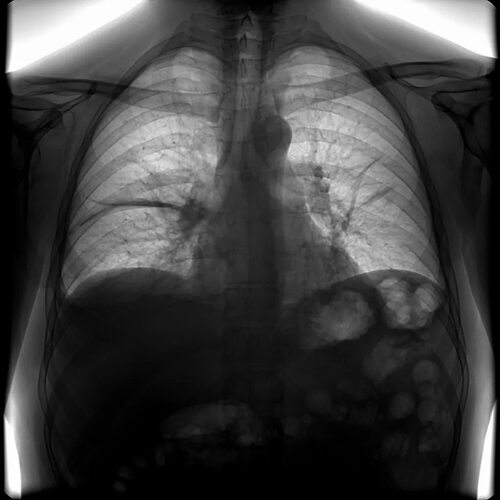

Ниже представлены фотографии, иллюстрирующие дисковидный ателектаз:

Дисковидный ателектаз - это состояние, которое может влиять на здоровье человека. Оно характеризуется...